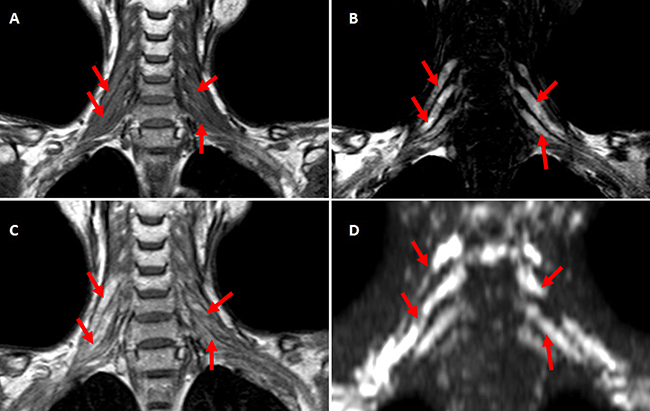

MRI of brachial plexus excluded tumor relapse in all the patients. Short tau inversion recovery (STIR) showed asymmetrical polyradiculopathy identified by unilateral or bilateral swollen in cervical roots extending through to the trunks. These abnormalities are common in C-5~C-8 levels but rare in the first thoracic vertebrae level (T-1). The injured nerves showed hyper-intensity on T1 and T2 weighted MRI images (Figure 4, Figure 5). The lesions of 8 patients showed enhancement at enhanced T1-weighted image (Figure 5C). Diffusion weighted MR imaging showed high intensity in the affected brachial plexus, indicating nerve edema (Figure 5D). Adjacent tissue surrounding the plexus was usually normal and intact.

Figure 5: A-D. The coronal MRI scan of one case with bilateral RIBP T1-weighted coronal MRI scan showed bilateral brachial plexus were swollen with hyper-intensity. (A) C-5~C-8 roots and corresponding trunks of brachial plexus showed prolonged T2 relaxation time at T2-weighted MR imaging (B), high intensity at Post-contrast T1-weighted imaging (C) and DWIBS (D) (indicated with red arrows).